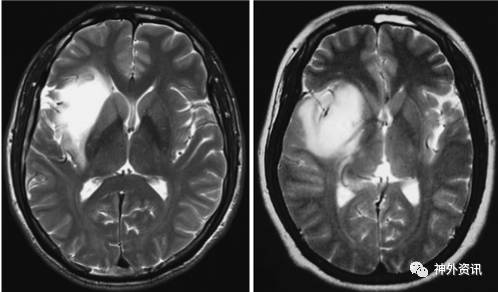

依据术前MRI扫描结果,将岛叶低级别胶质瘤分为累及壳核与未累及壳核两组(图1),应用多元分析模型对比两组患者的预后情况。

图1. 岛叶胶质瘤MRI图像:未累及壳核(左图)和累及壳核(右图)。

研究纳入211例原发性岛叶低级别胶质瘤患者,其中39例(46.9%)肿瘤累及壳核。累及壳核的肿瘤体积大于未累及壳核者(p<0.001),而且较少发生癫痫(p=0.04),累及壳核胶质瘤属野生型IDH1较多见(p=0.003),肿瘤全切的概率也较低(p=0.02)。单变量分析发现,术前KPS≥90分(p=0.007)、肿瘤切除程度高(p=0.008)、未累及壳核(p<0.001)和突变型IDH1(p<0.001)的患者预后明显较好(表1)。多因素分析发现,肿瘤切除程度高(p=0.035)、未累及壳核(p=0.014)和突变型IDH1(p=0.026)的患者预后更好。